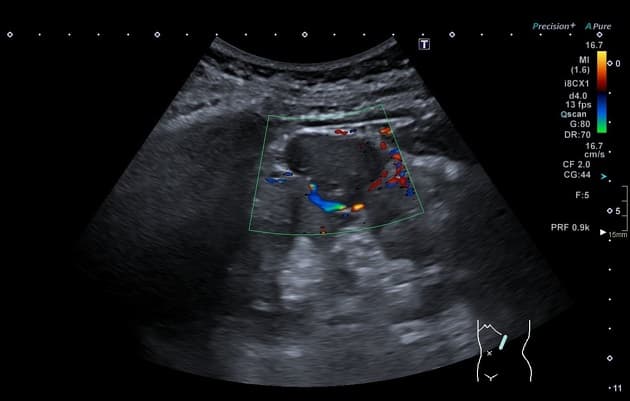

Đau hông phải và tiểu máu vi thể.

- Một khối nang khu trú một phần lồi ra ngoài (exophytic) kích thước 48 mm, thành dày ngấm thuốc (enhancement) và có các vách ngăn cùng các nốt ngấm thuốc lệch tâm (eccentric enhancing nodules) được ghi nhận ở phần giữa của thận phải.

- Một vài mạch máu tuần hoàn bàng hệ (collateral circulation) nhỏ giãn được ghi nhận trong khoảng gian thận (perinephric space).

- "Các đặc điểm hình ảnh chính bao gồm thành dày ngấm thuốc, vách ngăn ngấm thuốc và các nốt ngấm thuốc lệch tâm."